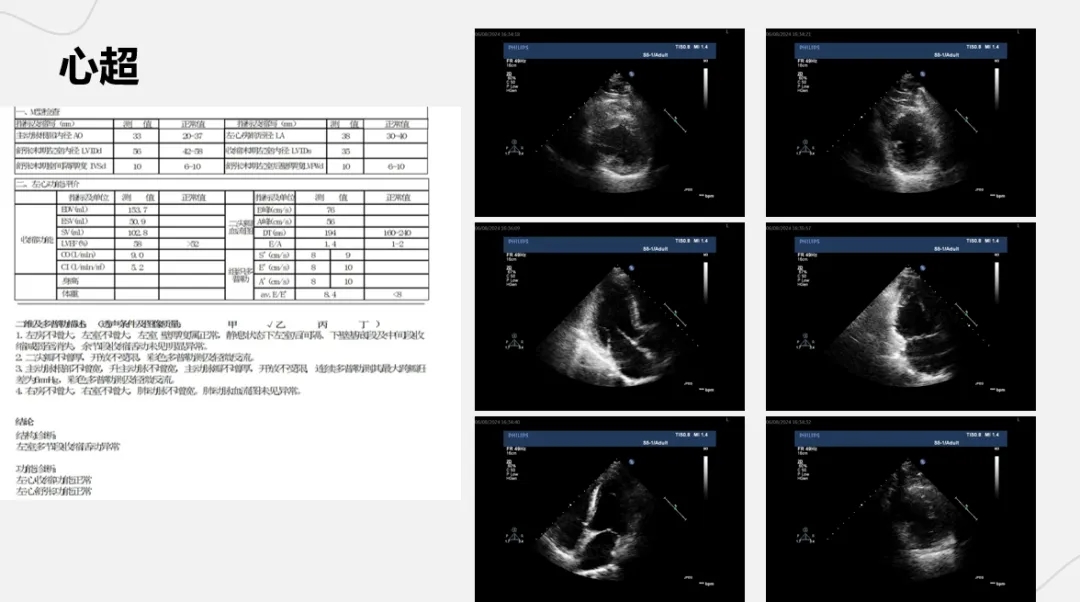

病例名称:诡异的非ST段抬高型心肌梗死

1、目前的诊断?下一步的检查和治疗计划

2、心肌标志物为何术后没有回落?进一步还需要做什么检查及治疗?